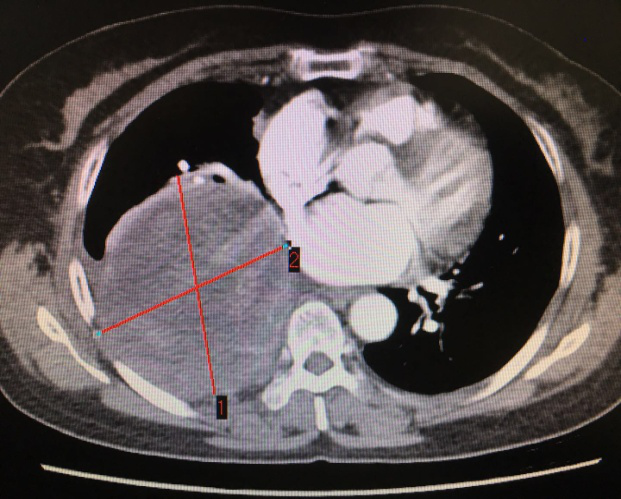

患者CT影像 (標記處為腫瘤)

李旭主任仔細為患者查體,經過嚴密的病情分析后,考慮腫瘤巨大,侵犯心包和下肺組織,決定先行肺穿刺,排除其他惡性腫瘤。最終穿刺病理顯示,陳阿姨患的是神經鞘瘤,這讓李主任松了一口氣:“還有手術的機會!”。